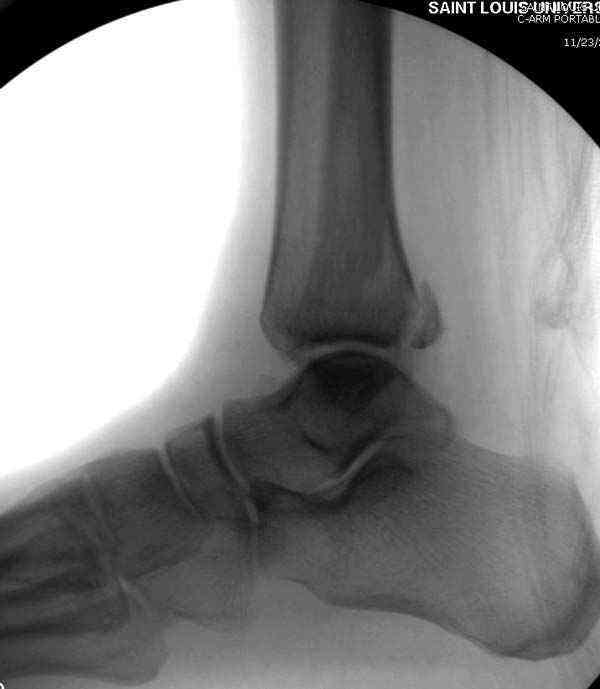

Нет первичных снимков, перелом очень низкий и под большим сомнением диагноз разрыва синдесмоза. Медиальная сторона отрепонирована на "хорошо" и, по-видимому, прорезание проволоки произошло во время операции. Без снимков трудно судить о высоте малоберцовой, а лодыжка находится в варусе. Лагирование получилось, но возле тонких шурупов передне-задний шуруп выглядит немного тяжеловато.

Медиальная лодыжка фиксируется каннюлированными лодыжечными шурупами перкутанно, а неточная репозиция (интерпозиция) является показанием к открытой технике. При больших вертикальных фрагментах нужны противоскользящие медиальные пластины.

Здесь несколько частных случаев: перелом голеностопа со сравнительными снимками и разрыв синдесмоза, а также медиальная Hook пластина.